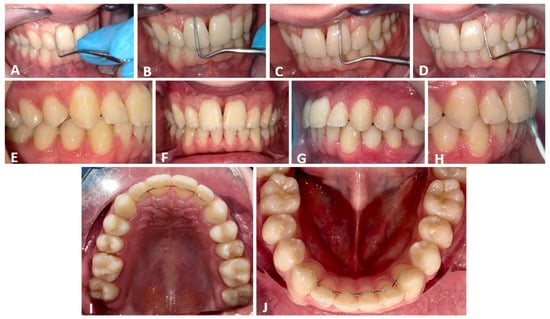

3. Results